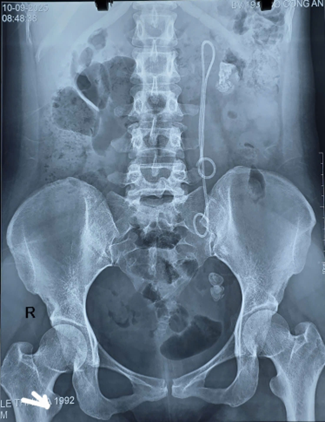

Bệnh nhân nữ, 33 tuổi, đến khám tại Phòng khám Tiết niệu – Nam khoa vì đau tức vùng thắt lưng trái kèm tiểu buốt. Qua thăm khám lâm sàng và cận lâm sàng, bệnh nhân được chẩn đoán: Sỏi thận trái + Sỏi niệu quản trái đoạn 1/3 dưới/ Còn Sonde JJ trái đặt 15 năm chưa rút

Năm 2010, bệnh nhân đã từng phẫu thuật lấy sỏi niệu quản trái và được đặt Sonde JJ. Tuy nhiên, do bận công việc, bệnh nhân đã quên lịch hẹn tái khám và rút JJ theo khuyến cáo.

Ảnh 1: Hình ảnh XQ của bệnh nhân

Trường hợp này, do Sonde JJ tồn tại tới 15 năm, bệnh nhân xuất hiện sỏi to ở nhiều vị trí, Sonde bám sỏi và di chuyển bất thường, khiến quá trình điều trị phức tạp và tiềm ẩn nhiều nguy cơ.